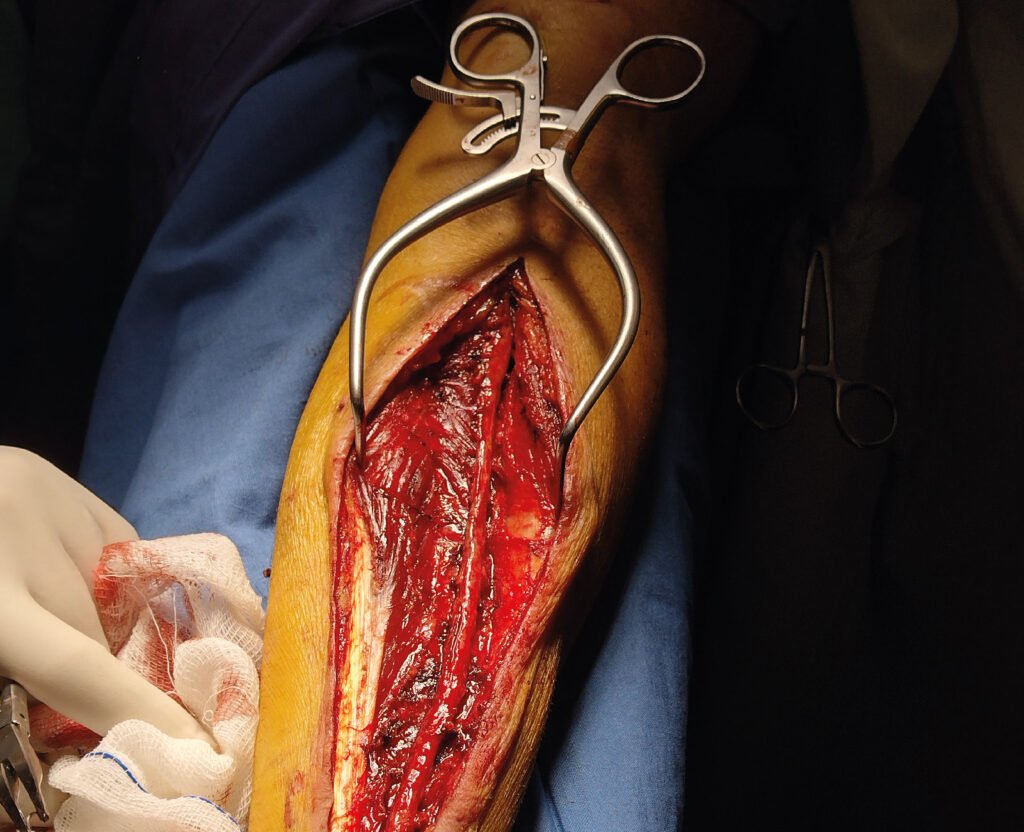

Cirugías reales

En esta sección se visualizarán cirugías reales en pacientes. Las fotografías por lo tanto

-si bien claras- en ocasiones privilegian la seguridad del paciente antes de

la exposición anatómica ideal.